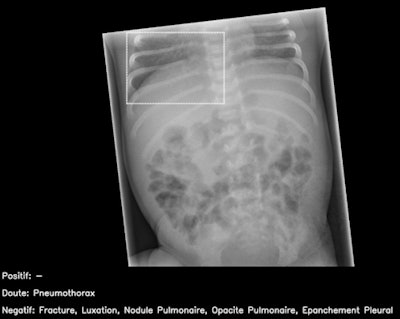

The AI candidate was Smarturgences v1.17.0, developed by French AI company Milvue and marketed since February 2020. It is used clinically in over 10 European hospitals and has been trained to assess MSK radiographs for fractures, swollen and dislocated joints, collapsed lungs, etc.

Allowances were made for images of body parts that the AI had not been trained in, and they were deemed uninterpretable.

Further training of the AI product is needed, particularly for cases considered "noninterpretable," such as abdominal radiographs and those of the axial skeleton, they said.